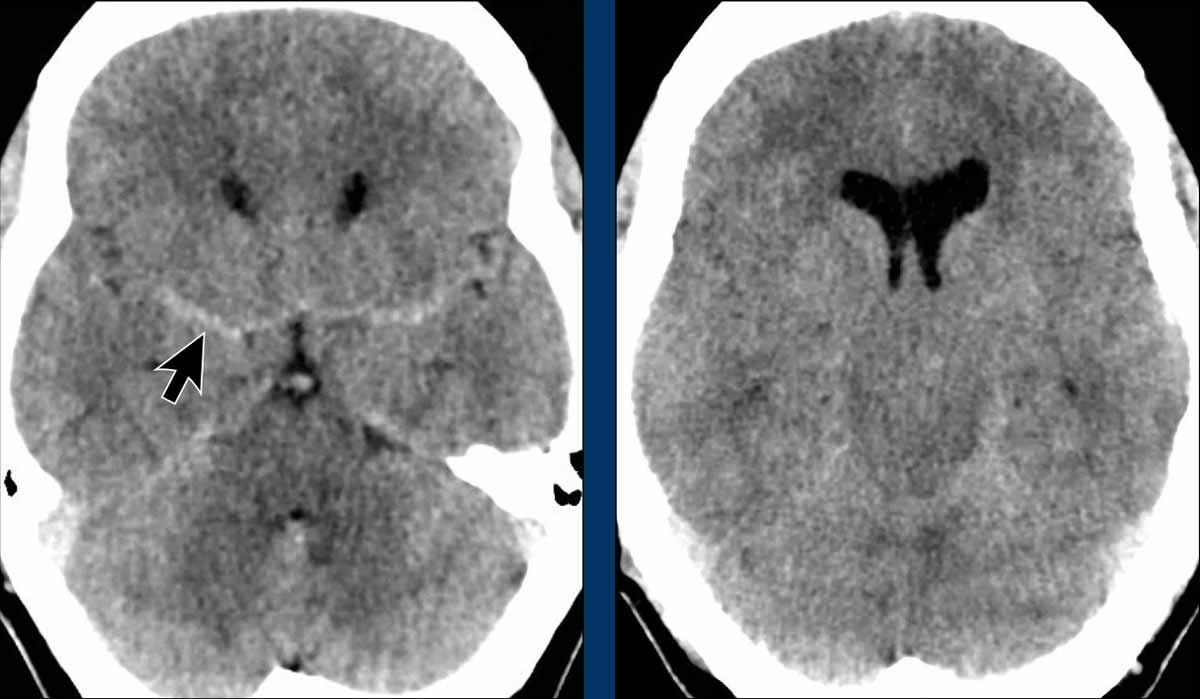

Các hình ảnh này của một bệnh nhân nam 57 tuổi, nhập viện với triệu chứng đau đầu và nôn mửa.

Bệnh nhân tỉnh táo và không có bất thường nào khi khám thần kinh.

Hình ảnh

Tỷ trọng đối xứng trong khoang dưới nhện ban đầu được xem là dấu hiệu của xuất huyết dưới nhện, đây là một nhận định hợp lý.

Có sự xóa mờ các bể nền, gợi ý thoát vị xuyên lều não theo chiều xuống.

CTA đã được thực hiện nhưng không phát hiện phình mạch nào.